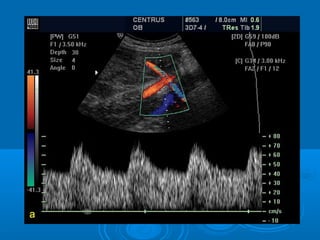

Color Doppler image of normal free loop of umbilical cord,

demonstrating the two arteries (red) and one vein (blue) at

28 weeks

Normal color Doppler frequency spectrum sampled

from the umbilical artery